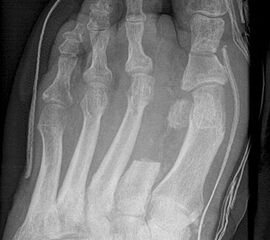

Wird der Ansatz des M. fibularis (peroneus) brevis bei Amputation des 5. Strahls entfernt, kommt es durch das muskuläre Ungleichgewicht zu einer Supination mit Vorfußadduktion und nachfolgend zu einer vermehrten Druckbelastung am Außenrand des Fußes (Abb. 30, 31). Um einer chronischen Ulzeration vorzubeugen, muss die Fehlstellung beseitigt werden, meist durch Transfer der Tibialis anterior Sehne.